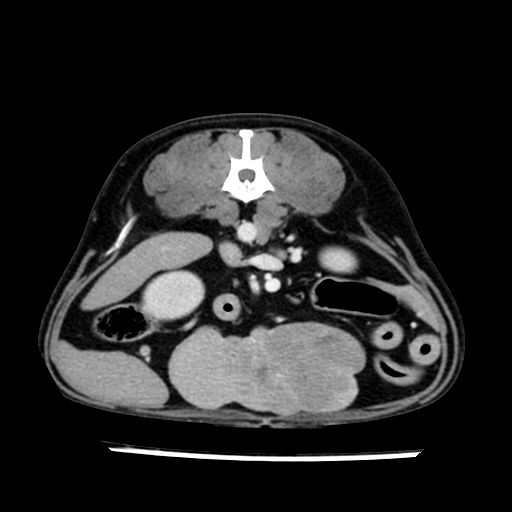

prescritto esame TAC

sequenza immagini limitata al fegato reni e surreni

le immagini ecografiche rispetto alla tac datano circa 7 mesi prima ,le surrenali sono normali nonostante il test acth sia risultato positivo .all’esame TAC dopo diversi mesi risultano aumentate armonicamente nel volume e si individua un forte sospetto di adenoma ipofisario .

sospetto adenoma ipofisario vs. meno probabilmente meningioma della base; intertiziopatia polmonare; lesione espansiva epatica, verosimilmente del lobo laterale sinistro, di sospetta natura neoplastica; lesioni spleniche di natura da definire; iperplasia/ipertrofia delle ghiandole surrenali, bilateralmente; vertebra di transizione del rachide toracico; tenosinovite cronica del muscolo bicipite brachiale di destra.